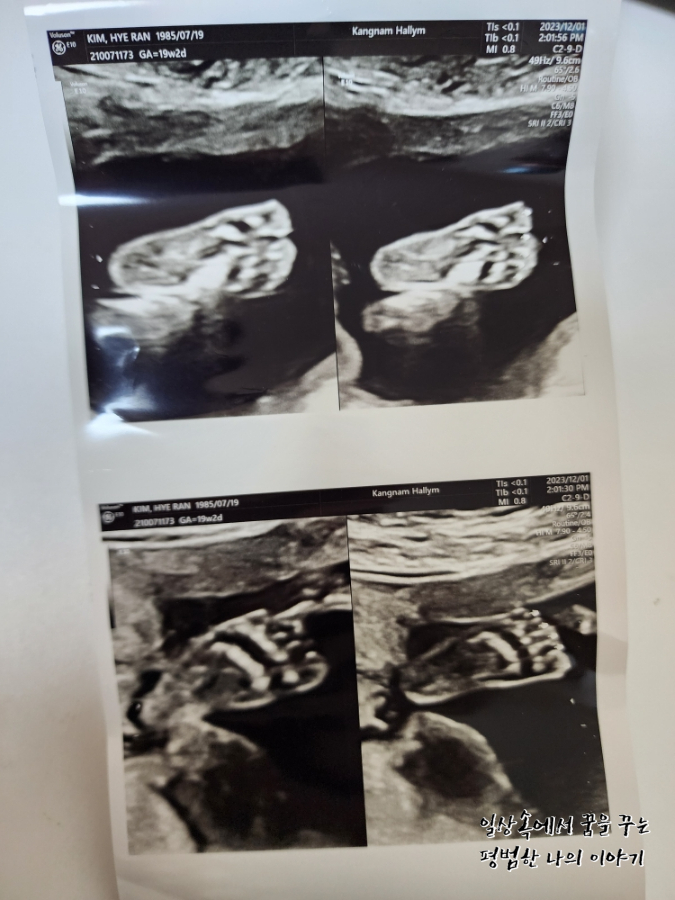

4주 만에 방문한 병원에서 삼등신이 된 아기를 만날 수 있었다. 이번에는 정확한 성별을 들을 수 있지 않을까 내심 기대했는데 아니나 다를까 정확하게 딸이라고 성별을 알려주셨다. 남편은 딸이라는 얘기를 듣자마자 이전부터 생각해뒀던 딸 이름으로 아기를 부르기 시작했다. 태동은 아직 느껴지지 않는데 이안이 때도 좀 늦게 느끼기 시작한 편이라 마음이 조급하지는 않다. 지금 걱정인 건 이안이 때는 임신 후반부터 아래쪽이 뻐근하고 아팠는데 둘째는 그 뻐근함이 너무 빨리 찾아와서 16주 정도 됐을 때부터 오후가 되면 붓기 시작해 서 있는 것조차 힘들어지기 시작했다. 의사 선생님께 괜찮은 거냐고 물어보니 다행히 아기한테는 아무런 영향이 없다고 하셨고 해결할 수 있는 방법은 역시나 출산뿐이라고 하셔서 버티는 수밖에 없겠구나 싶었다. 약간 자궁에 피고임이 있어 걱정이 되었는데 의사 선생님이 무리하지 말라고 하시더라. 자궁 내에 있는 피고임이라 증상이 악화돼도 알 수 있는 방법이 없기 때문에 배가 너무 아프거나 하면 바로 병원으로 오라고 하셨다.